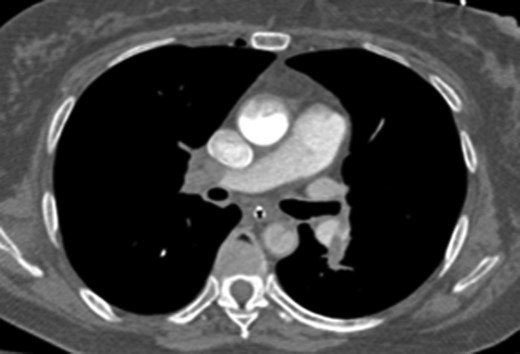

Once stable, imaging confirmed PE (Fig. 2) with a RV to left ventricle (LV) ratio of 2.1 (Fig. 3). The patient was then admitted to the ICU requiring inotropic support. Approximately 4 h later, the patient had concerning features of abdominal compartmental syndrome with increase abdominal distention and bladder pressures >25 mmHg was noted. Repeat imaging showed large volume hemoperitoneum emanating from the left hepatic lobe (Fig. 4). The patient underwent a decompressive laparotomy with a non-anatomic liver resection of segments I and II and temporary abdominal closure. Due to concerns of distal limb ischemia of the arterial cannulation site, an 8-Fr reperfusion cannula was placed in the left superficial femoral artery (SFA).

CTA abdomen performed when the patient had abdominal compartmental syndrome requiring massive transfusion protocol. CTA showing extensive hemoperitoneum with active extravasation from the left lobe of the liver.